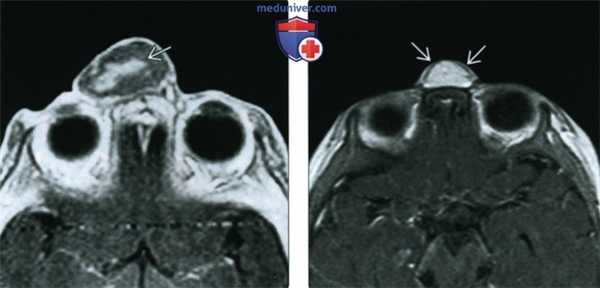

(Слева) При аксиальной МРТ Т1 С+ определяется контрастное усиление в центре большой экстраназальной глиомы, слегка смещенной от средней линии. Накопление контраста в экстраназальной глиоме нетипично.

(Справа) При аксиальной МРТ Т1 С+ визуализируется хорошо отграниченная срединная экстраназальная глиома спинки носа с диффузным контрастным усилением. Настолько выраженное накопление контраста - редкий признак глиомы носа.